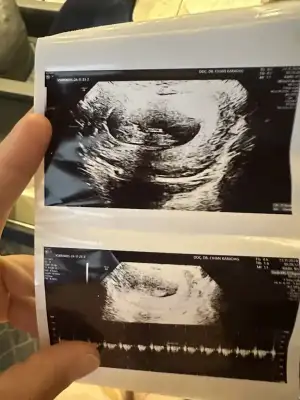

Kızlar sabahtan sırtım ağrıyor tutulmuştur diye önemsemedim şimdi lavaboya gittim pembe kırmızı gibi az bı kan geldi ne yapmalıyım korkudan ölecem

Sana bu mesajı yazdıktan bi kaç saat sonra baya kahverengi akıntım oldu yatayım dinleneyim dedim geçer ama pembe kırmızıya döndü hemen acile gittim. Bebekte kesede bi sorun yoktu çok şükür kalp atışı vs herşey normaldi. Progestan başladım ve dinlenmeye çalışıyorum. Doktor sebebini söylemiş miydi ? Senin de 8. Haftalardı sanırım yanlış hatırlamıyorsam.Bence çok vakit kaybetmeden acile git bir şekilde müdahale edilir ya da varsa bi sorun tespit edilir. En azından için rahat eder.